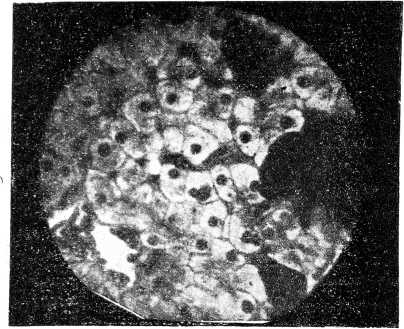

Рис.3. Клетки печени, сфотографированные при увеличении в 420 раз.

Рис. 4. Коллоидный зоб при увеличении в 420 раз.

Прилагаемые при сем микрофотограммы могут свидетельствовать, о том, что при этой комбинации сравнительно простых приспособлений можно получить удовлетворительные результаты, и всякий врач, имея этот несложный инструментарий может, при желании, заняться микрофотографией. Микрофотограммы исполнены на русской бромо-серебряной бумаге невысокого качества; имея заграничную бумагу, лучшего качества, можно получить отпечатки гораздо контрастнее. Снимки получены: с помощью сухих систем микроскопа, но хорошие результаты получаются при фотографировании бактериологических препаратов и иммерзионными системами.